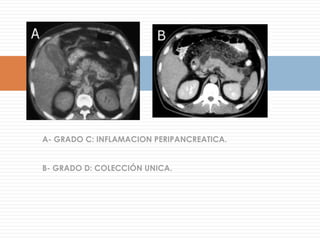

En el TAC C se observa engrosamiento de la pared, aumento de la densidad de la bilis y en el TAC D el cálculo impactado en el cístico. La TAC es un excelente método para colecistitis aguda de presentación inusual y las formas más graves por la distorsión que se produce en la ecografía (ileo asociado, distorsión de la anatomía del lecho vesicular)La colecistitis alitiásica se debe pensar en otro contexto clínico (quemado grave, ICC, SIRS, operados, etc.)

En el TACC se observa engrosamiento de la pared, aumento de la densidad de la bilis y en el TAC D el cálculo impactado en el cístico. La TAC es un excelente método para colecistitis aguda de presentación inusual y las formas más graves por la distorsión que se produce en la ecografía (ileo asociado, distorsión de la anatomía del lecho vesicular)La colecistitis alitiásica se debe pensar en otro contexto clínico (quemado grave, ICC, SIRS, operados, etc.)